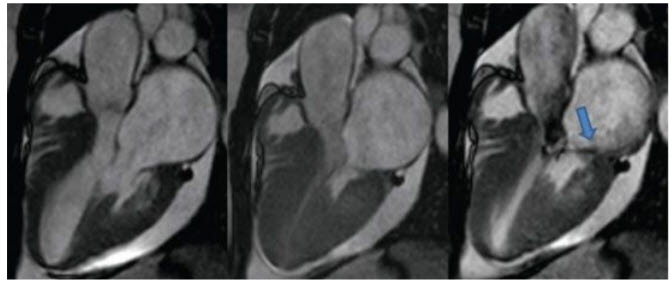

A 67-year-old woman is referred to your office for evaluation of a heart murmur. She describes symptoms of significant and limiting exertional dyspnea. On examination, she is normotensive. Pulse rate is 67 bpm and regular. Cardiac examination reveals a sustained but nondisplaced PMI. S1 and S2 are normal. An S4 is present. A loud III/VI systolic ejection murmur is heard throughout the precordium. Carotid upstrokes are delayed and diminished. An echocardiogram is performed (Fig. below).

Continuous-wave Doppler evaluation reveals a 4.5-m/s jet across the LVOT.

TEE. The echocardiogram reveals a normal-appearing aortic valve. Yet, the profile of the continuous-wave Doppler jet is more consistent with a fixed obstruction, as opposed to the dagger shape of dynamic obstruction. These findings are suggestive of the presence of a subvalvular membrane. TEE would be useful to better delineate this area and identify the membrane. The patient already has a 5-m jet in the absence of systolic anterior motion; therefore, it would not be prudent to use provocation with amyl nitrate. A stress echocardiogram would have no diagnostic value and may have some risk in the setting of symptomatic LVOT obstruction. One should always consider contamination with an MR signal; however, the physical examination is consistent with outflow tract obstruction and the continuouswave Doppler signal begins after the QRS (after isovolumetric relaxation) consistent with outflow tract obstruction. The MR signal will begin earlier relative to the QRS (through isovolumetric contraction).